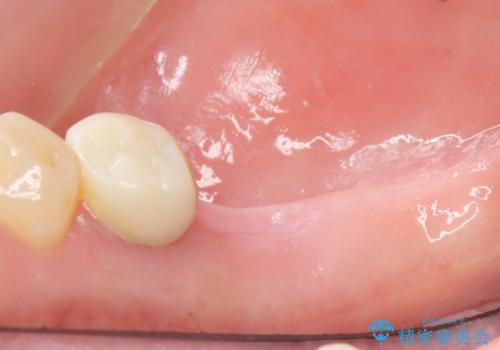

患者様のご希望により、右下大臼歯2本(右下76)のインプラント治療、右下小臼歯(右下5)の根管治療及び補綴治療を行いました。

割れていた歯の周囲組織の炎症が強く、骨の厚みが薄かったため、インプラント埋入時に骨増生(GBR)を行いました。

奥歯でしっかり噛むことができるようになり、喜んで頂けました。